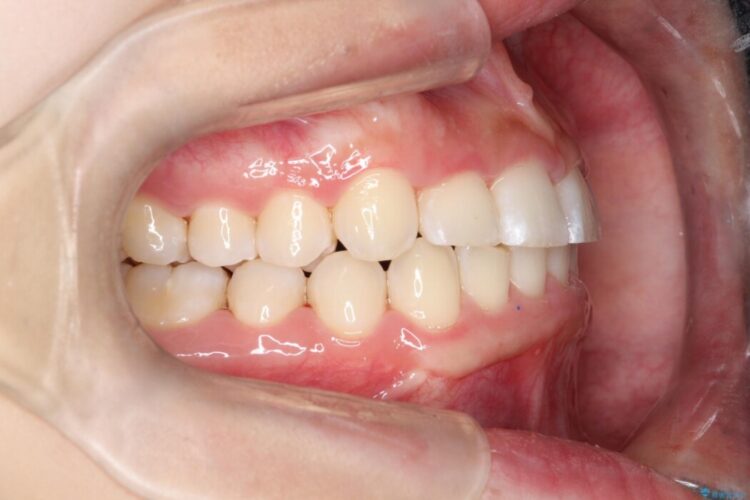

口を開けた時に下の前歯が見えない状態、ガタガタの歯並びに悩んでいるとの主訴で来院されました。

最終的な仕上がりでは下顎の前歯がきれいに見えるようになり患者様には大変喜んでいただきました。